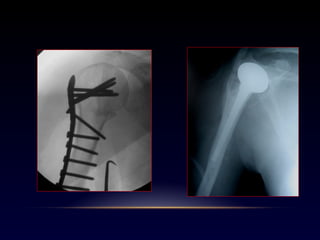

Fx cadera

Mujer 86a, HTA, DM

Hombre 98a, HTA

Cardiopatía, DM